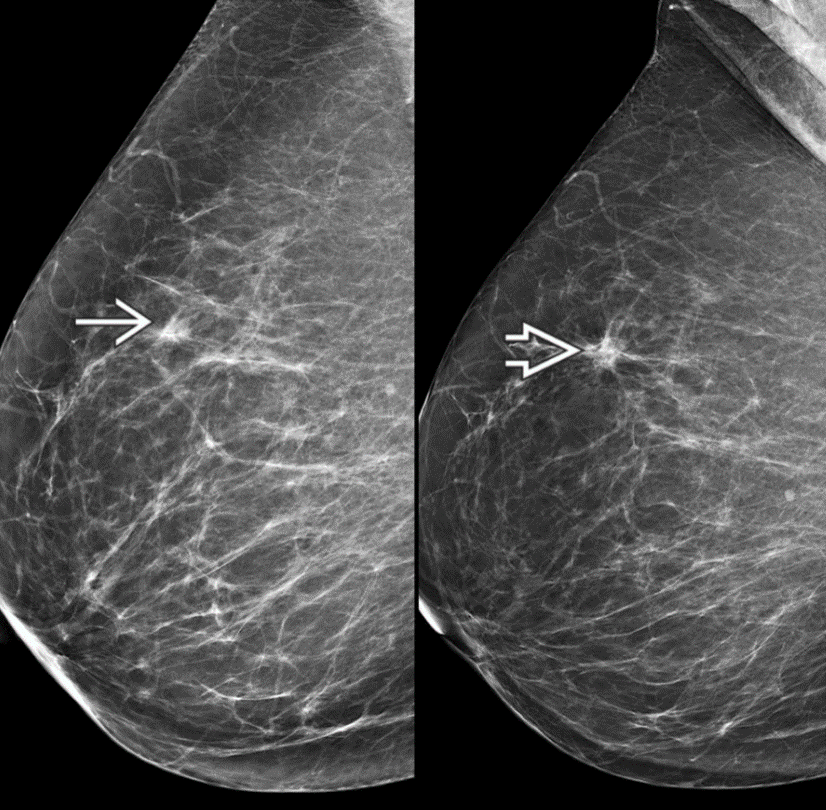

A tubular carcinoma is a special type of well-differentiated invasive ductal carcinoma (IDC) composed of well-differentiated tubular structures with open lumina lined by a single layer of epithelial cells. It presents as a small, spiculated mass on mammography and may be stable for years. The 5-year survival is 95-98%.

Mammo: Irregular spiculated mass, architectural distortion, asymmetry

US: Irregular, spiculated mass with indistinct margins